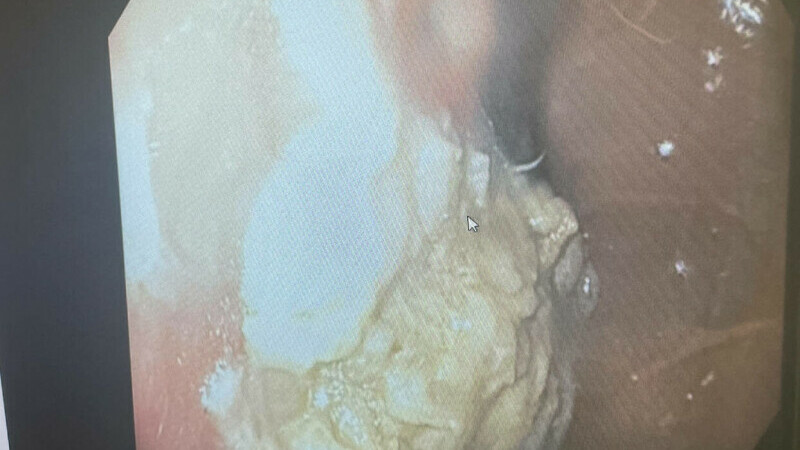

Medicii nu au spus dacă firele de aur au fost îndepărtate, dar, în cazuri anterioare, astfel de fire au fost lăsate la locul lor. Asta nu este întotdeauna lipsit de riscuri, deoarece au dus la formarea de chisturi în cazuri similare.

De asemenea, firele pot migra în interiorul corpului, iar fragmentele pot deteriora țesutul învecinat. De exemplu, firele de aur introduse în spatele unei femei sud-coreene în vârstă de 75 de ani au migrat în partea inferioară a piciorului drept pe o perioadă de 10 ani, provocând celulită - o infecție profundă a pielii.